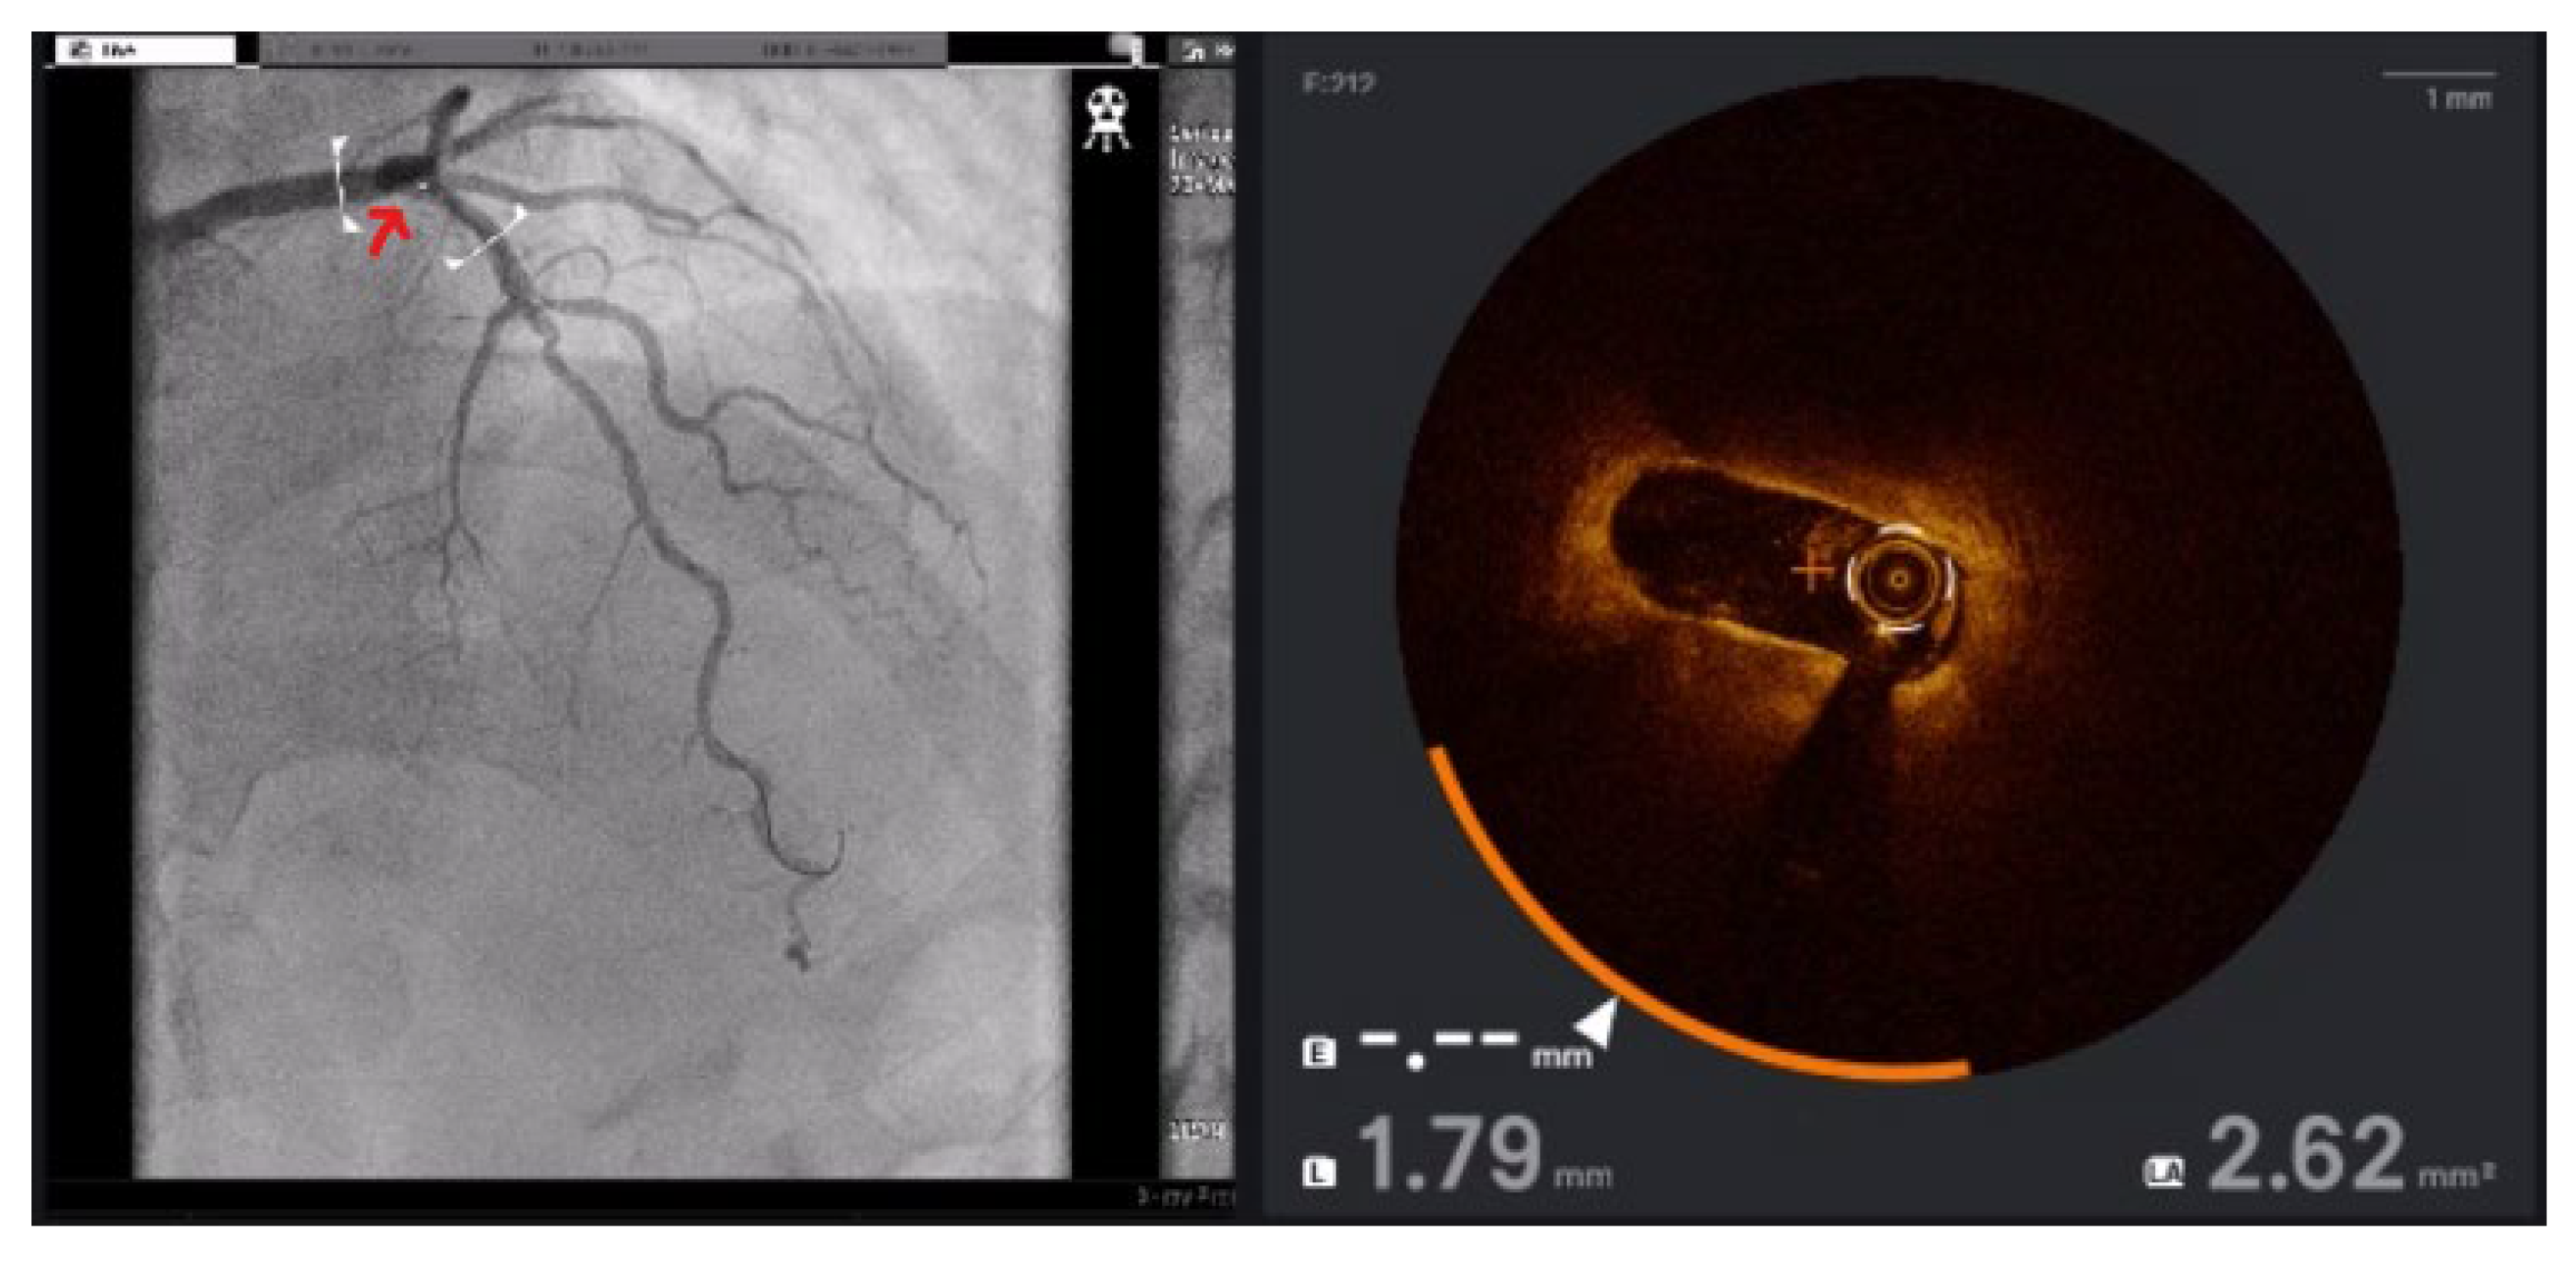

To address these challenges, adjunctive imaging modalities have been adapted to enable ultra-low contrast PCI. Intravascular ultrasound (IVUS) provides detailed cross-sectional images without reliance on contrast media (Figure 1) and is recommended in complex interventions [5,6]. OCT provides high-resolution plaque characterisation and stent assessment (Figure 2), but requires flushing, typically with contrast media; however, substitutes such as low-molecular-weight dextran and heparinised saline have shown promise as alternatives [51,52,53,54]. DCR software overlays a live coronary roadmap onto the fluoroscopic image, enabling navigation of coronary tools and stent delivery without repeated contrast injections (Figure 3) [7,55]. While these modalities provide valuable anatomical information, they remain dependent on fluoroscopic platforms and do not eliminate contrast use entirely, highlighting the potential role for complementary navigation technologies such as EAMS.

Figure 2. OCT of the left anterior descending (LAD) artery. Red arrow indicates the referenced OCT segment correlating with the angiogram. OCT reveals severe proximal LAD stenosis not readily apparent on angiography.